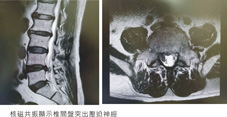

55歲朱伯伯,因搬重物後發生坐骨神經痛,核磁共振檢查顯示有突出之椎間盤軟骨壓迫神經,住院接受經皮內視鏡經椎間孔腰椎椎間盤切除手術(PETLD),術後恢復良好,疼痛大幅改善,當天即下床活動,隔日辦理出院回家。